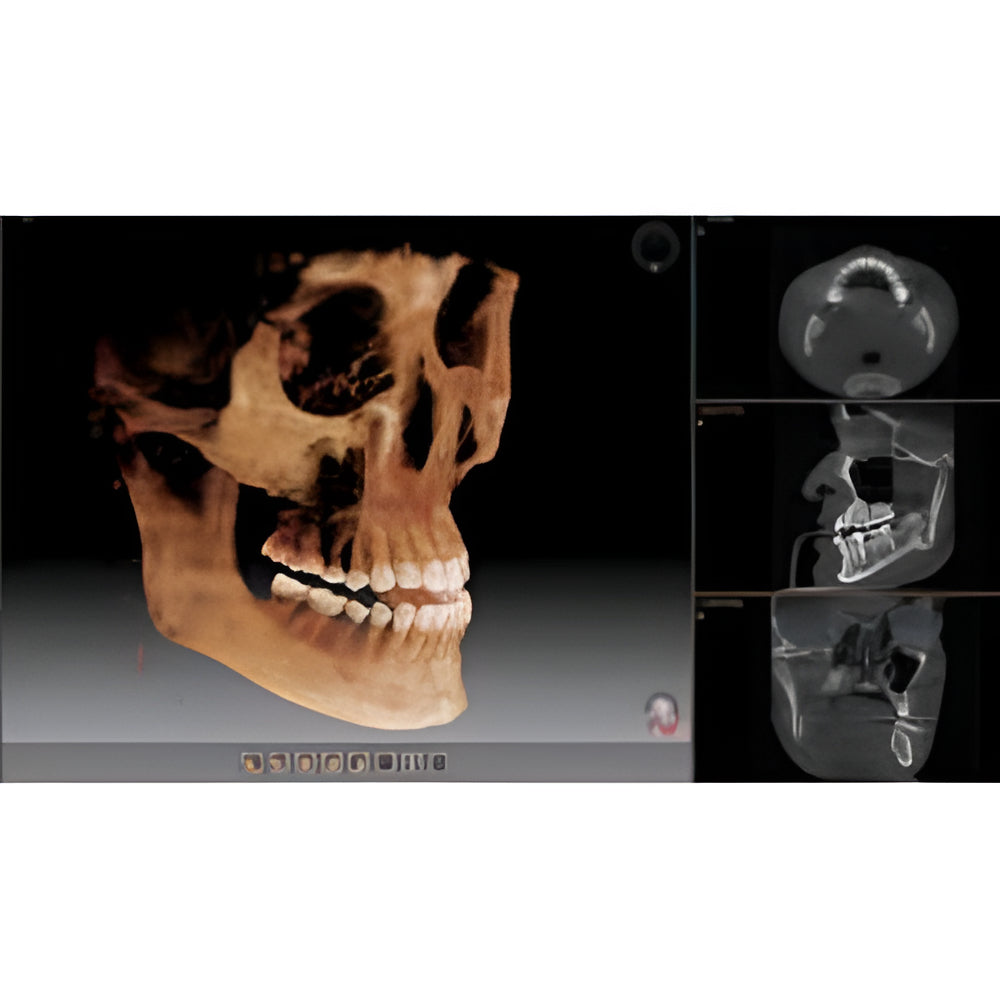

The Vatech PaX-i3D Green panoramic plus cone beam system delivers large field of view (up to 15 x 15 cm) dental CBCT scans in addition to standard 2D panorex and extraoral bitewing X-ray images. This Vatech CBCT machine features the innovative green CT technology which minimizes patient dose, while the Rapid Scan feature delivers high-quality 3D cone beam scans in just 5.9 seconds. A quick exposure time helps to minimize artifacts and motion, while at the same time reducing patient dose, making your imaging process more efficient and safer.

- Field Of View: 5x5, 5x8, 8x8, 12x9

- EZ3Di Imaging Software with License

- 3D Cone Beam

- Large FOV

- Cephalometric